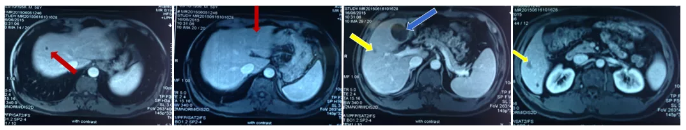

MRI复查结果:

病灶变化情况

2017.12复查 MRI示:肝左外叶见一斑片状稍长T1稍长T2信号影,横截面约1.4cm×1.4cm,增强扫描边缘强化。

肝脏MRI检查